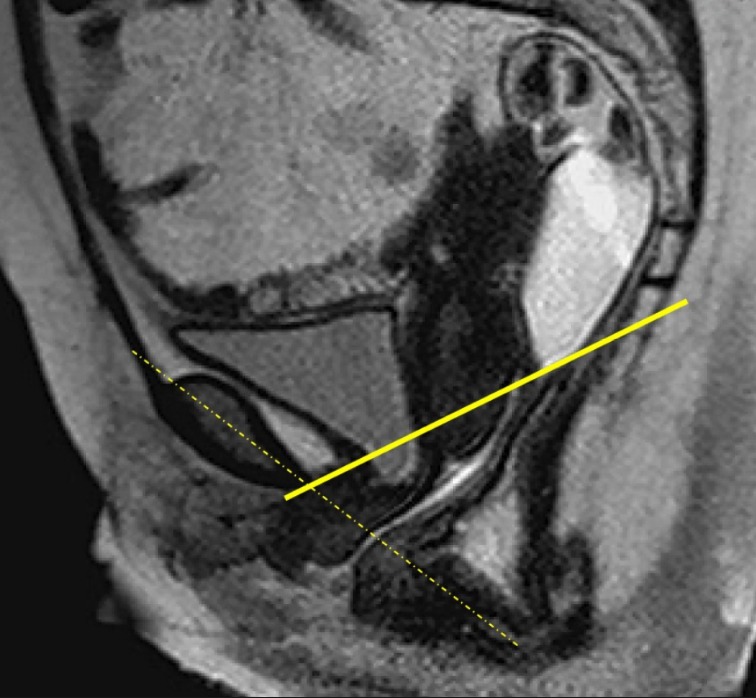

Las segundas opiniones independientes en resonancia magnética de pelvis ginecológica ayudan en decisiones médicas importantes, de forma discreta, estructurada y rápidamente disponibles.